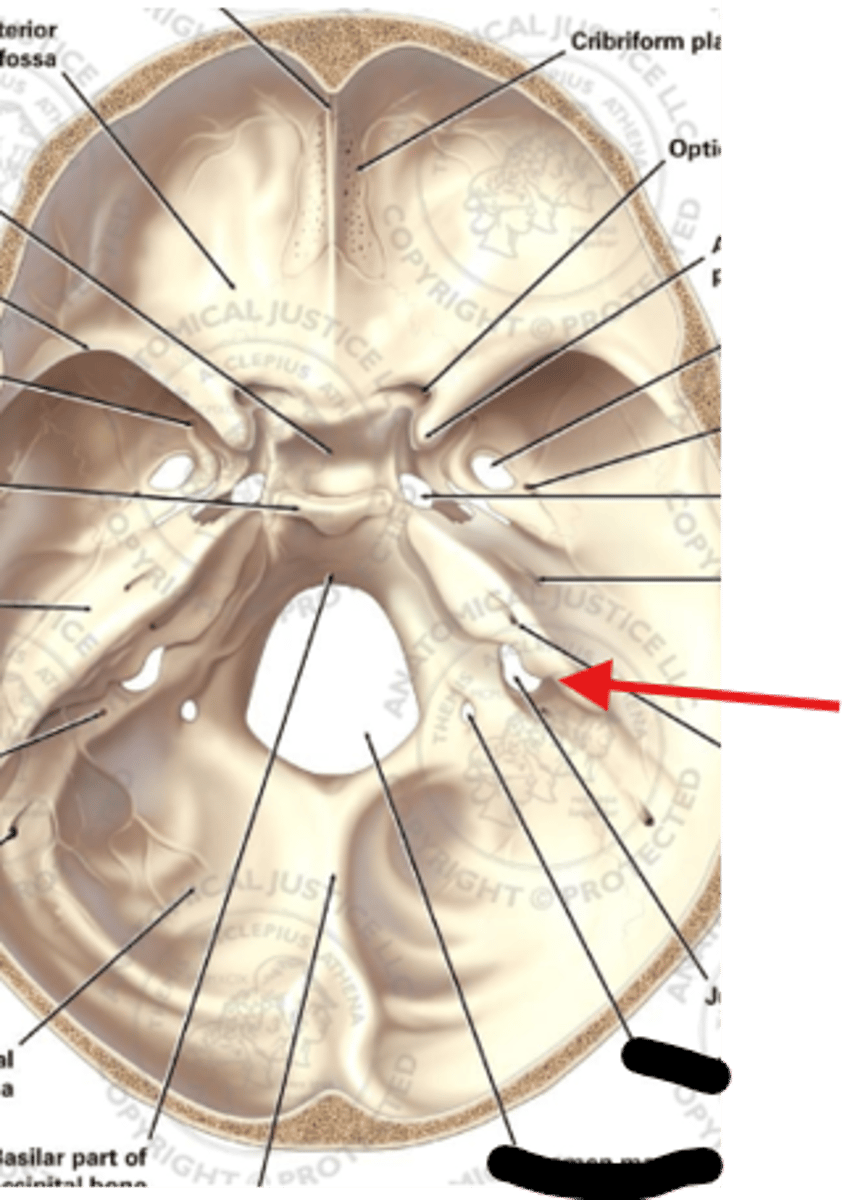

What is the name of this foramen?

Name something that goes through this foramen?